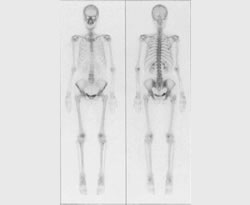

RI検査は、患者さんに放射性医薬品を投与することから始まります。投与された放射性医薬品が、目的とする臓器や組織に集まったところを、ガンマカメラという装置で撮影します。全身像や断層像、体内のさまざまな臓器の働きなどの情報を得ることができます。

3.撮像開始:体外よりガンマカメラを用いて、集積したRI画像を撮像します。ほとんどの場合寝ているだけで済みます。検査時間は短いもので30分、長いもので90分くらいかかります。時間を追って、何度か撮像する場合もあります。

骨シンチ (骨の腫瘍・炎症・骨折など)